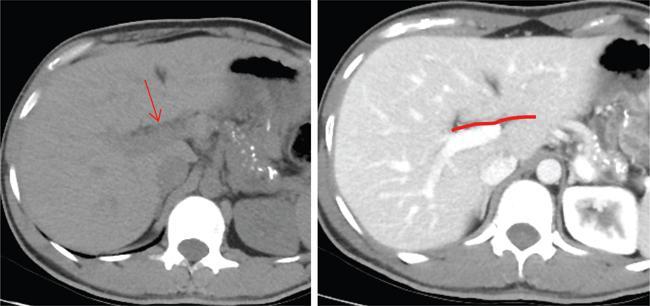

Ritu K. Kashikar, Shrinivas B. Desai Imaging is the mainstay of noninvasive diagnosis of the spectrum of abdominal pathologies or proving absence off thereof. Knowledge of normal anatomy and important normal variants is thus essential for the radiologist in order to avoid misinterpretation or erroneous diagnosis. This chapter highlights the normal anatomy of the hepatobiliary systems including the blood vessel and draining ducts and discusses relevant anatomical variants which may have important clinic implications. The liver is the largest abdominal organ, occupying the right upper abdominal quadrant and is in close approximation with the diaphragm, stomach and the gallbladder. It is largely covered by the costal cartilages. The liver is encapsulated by Glisson’s capsule which is a dense layer of connective tissue. It is covered by peritoneum, except in the regions of gallbladder fossa, fossa for inferior vena cava (IVC), and the bare area. The bare area is the posterocranial aspect of the liver, adjacent to the dorsal body wall, which is not covered by peritoneum. The liver has two surfaces, the convex diaphragmatic surface and a concave visceral surface. The slit in the hepatic hilum is called the porta hepatis and is penetrated by the right and left hepatic ducts (LHDs), hepatic artery and portal vein (PV). The distal portion of the lesser omentum is called the hepatoduodenal ligament and contains the common bile duct (CBD), hepatic artery, PV, nerves of liver and lymphatics. The liver has dual blood supply with hepatic artery providing 25% of hepatic blood and rest by portal vein (Fig. 9.2.1). Five ligaments connect the liver to the undersurface of the diaphragm. These include the falciform, the coronary and two lateral ligaments, all of which are peritoneal folds. The fifth ligament is a fibrous cord-like structure and represents the obliterated umbilical vein. The peritoneum invaginates into the liver parenchyma leading to formation of fissures. There are four normal fissures: fissures for the ligamentum teres, ligamentum venosum and gallbladder and the transverse fissure (Fig. 9.2.2). The liver is organized into microscopic functional units called lobules or acini. A central terminal hepatic venule surrounded by four to six terminal portal triads form a polygonal unit called the hepatic lobule. The terminal portal triad branches line the periphery of the unit. Between the terminal portal triads and the central hepatic venule the hepatocytes are arranged in one cell thick plates, surrounded by sinusoids. The blood flows from the terminal portal triad through sinusoids into terminal hepatic venule. Bile formed within the hepatocytes empties into terminal canaliculi which coalesce into the bile ducts (Fig. 9.2.3). This structure of the functional hepatic unit forms the basis of various functions of the liver. The normal relations of the liver are: The liver can be divided into right, left and caudate lobes. The right and left lobes are separated by the interlobular fissure and is oriented along a line passing through the gallbladder fossa inferiorly and the middle hepatic vein (MHV) superiorly (Fig. 9.2.4). This plane runs from the left of the IVC to the left of the gallbladder fossa and is a called the Cantlie’s line. Use of standardized, segmental anatomy is imperative because it facilitates communication and treatment planning. The segmental anatomy of liver is primarily based on vascular anatomy. The right lobe is divided into anterior and posterior sectors by of the right hepatic vein (RHV). The left lobe is divided into medial and lateraI sectors by an oblique plane connecting the left hepatic vein (LHV) and the falciform ligament. The liver is divided into upper and lower segments at the level of main portal vein (MPV) bifurcation (Fig. 9.2.5). Various systems are used in classification of liver anatomy. These are discussed in Table 9.2.1. The Couinaud’s system is the most commonly used and divides eight sections/segments which are discussed in details below (Table 9.2.2). 1. Segment 1 – Caudate lobe Bounded anteriorly and medially by the fissure for ligamentum venosum (Fig. 9.2.6). 2. Segment 2: Superior segment of the left lateral sector/section Bounded medially by falciform ligament and inferiorly by plane of MPV, also known as the posterior lateral sector (Bismuth, FCAT) (Fig. 9.2.7). 3. Segment 3: Inferior segment of left lateral sector/section Bounded medially by the falciform ligament and superiorly by the plane of the MPV bifurcation, also referred to as lateral anterior sector (Bismuth, FCAT) (Fig. 9.2.8). 4. Segment 4: Left medial sector/section Bounded laterally by falciform ligament and medially by Cantlie’s line (Fig. 9.2.9). 5. Segment 5: Inferior segment of the right anterior sector/section Bounded anteriorly by the gallbladder fossa and posteriorly by the plane of the RHV, superiorly bounded by the plane of MPV bifurcation (Fig. 9.2.10). 6. Segment 6: Inferior segment of the right posterior sector/section Bounded anteriorly by plane of the RHP and superiorly by the plane of the MPV bifurcation (Fig. 9.2.11). 7. Segment 7: Superior segment of the right posterior sector/section Bounded anteriorly by the plane of the RHV and inferiorly by the plane of the MPV bifurcation (Fig. 9.2.12). 8. Segment 8: Superior segment of the right anterior sector/section Bounded anteriorly by the plane of the gallbladder fossa and MHV, posteriorly bounded by the plane of the RHV and inferiorly by the plane of the MPV bifurcation (Fig. 9.2.13). Owing to its broad area of contact with the anterior abdominal wall, the liver is an ideal organ for evaluation with sonography. Ultrasound is commonly used for evaluation of size of the liver. On longitudinal scans obtained through the midhepatic line, if the liver measures 13 cm or less, it is normal in 93% of individuals (Fig. 9.2.14). The size of liver in various planes is discussed in chapter on normograms. When the area of contact between the liver and the anterior border of the right kidney, exceeds below two thirds of the kidney, the liver is considered as enlarged. The normal liver is homogeneous with fine echoes and appears evenly bright. The hepatic veins, PV and fissures interrupt the homogeneity of the liver parenchyma (Fig. 9.2.15). The parenchymal echogenicity may vary depending on the equipment, transducer and gain settings and should be judged by comparison with internal references like right renal cortex, body of the pancreas and PV walls. When compared with the adjacent normal right renal cortex the liver normally appears hyperechoic or isoechoic. The pancreas in a young individual is hypoechoic compared to the liver, and isoechoic in middle aged adults. As age progresses and fatty infiltration of the pancreas occurs, the pancreas appears hyperechoic to the liver. The liver is hypoechoic to the spleen. The normal liver reveals a density of 55–65 HU on nonenhanced scan and should appear homogenous with the exception of hypodensity in the regions of vessels and fissures. The liver parenchymal enhancement is minimal the arterial phase, with increase in density by only approximately 10 HU. This phase is usually to access vascular anatomy and to detect neovascular enhancing lesion like HCC, metastasis. Considering the fact that 75% of heptic venous supply is from the PV, the normal hepatic parenchyma shows maximum enhancement in the portal venous phase. During the venous/delayed phase the hepatic attenuation starts falling (Fig. 9.2.16). The hepatic fissures appear as linear fat containing structures. All the four fissures are well identifies on CT (Figs. 9.2.17–9.2.20). Normal liver should demonstrate uniform T1 signal similar or isointense to the paraspinal muscles and slightly hyper intense to the spleen. No signal drop should be seen on in or opposite phase. On T2W1 images liver appears slightly hyperintense to paraspinal muscles, isointense to pancreas and hypointense to spleen (Fig. 9.2.21). Following administration of extracellular contrast agents the normal liver parenchyma enhances on PV phase similar to that seen on CT. The arterial phase is preserved to determining vascular anatomy, variants and tumoural enhancement. Gadoxetic acid (Eovist) and gadobenate dimeglumine (MultiHance) are hepatobiliary agents showing excretion by the liver. In the case of gadoxetic acid, hepatic excretion is ~50%, which allows imaging in the hepatobiliary phase at ~20 minutes following injection. Gadobenate has only 3%–5% biliary excretion with hepatobiliary phase at approximately 40 minutes (Fig. 9.2.22). This property makes these agents useful in detection of nonhepatocyte containing lesions which appear hypointense to background liver on hepatobiliary phase. Hepatic anatomic variants are relatively common and represent normal interindividual variation of liver morphology. Normal Anatomic Variants Anatomic anomalies Accessory and pseudofissures may be seen in the liver. True accessory fissures result from infolding of the peritoneum usually along the undersurface of the liver and are rare. The inferior accessory fissure is the commonest accessory fissure and divides the posterior segment of the right hepatic lobe into lateral and medial portions. Diaphragmatic slips may cause indentation over the liver surface and are not commonly seen on imaging (Fig. 9.2.23). Leftward extension of the lateral segment of the left hepatic lobe appearing as a crescentic density that wraps around the spleen is referred to as sliver of liver. The left lobe of the liver may exhibit various forms: leaf like; spatular; truncated pyramid/wedge shaped; and a bifid appearance (Fig. 9.2.24). Elongated left lobe may be mimic splenomegaly, perisplenic hypoechoic collections or less commonly tumours. Imaging clues to diagnosis are establishing contiguity with liver and visualization of parenchymal vessels coursing through. The portion of the liver that extends medially from the right lobe between the IVC and fissure for ligamentum venosum is called the caudate lobe. The caudate lobe is divided inferiorly into a lateral caudate process and a medial papillary process. The medial papillary process projects medially towards the pancreatic head and has applied importance (Fig. 9.2.25). Riedel’s lobe is a tongue-like projection from the anterior aspect of the right lobe and the most common accessory lobe of the liver. It is seen most frequently in asthenic women. The reported prevalence of RL, ranges from 3.3% to 14.5% and the prevalence is higher in women than in men. It can be 20 cm or more in length and may extend up to the iliac fossa. It is usually asymptomatic and is discovered incidentally (Fig. 9.2.26). Accessory liver lobes are defined as a supernumerary lobe of normal hepatic parenchyma in continuity with the liver. This is a rare entity and usually occurs as a result of congenital ectopic hepatic tissue, although rarely may occur as a result of trauma or surgery. Various systems are proposed for classification of ALL. Another method of classification has been proposed based on biliary drainage and presence or absence of capsule. Accessory lobes can be readily diagnosed and characterized on CT or magnetic resonance imaging (MRI) done for related or unrelated conditions. CT shows the lesion as a soft–tissue density mass attached to the liver and isodense to the organ. The portal/hepatic venous branches can be seen coursing through it, in contiguity with the liver (Fig. 9.2.27). The coeliac axis trifurcates into common hepatic, splenic and left gastric arteries at the level of T12–L1. The common hepatic artery becomes the proper hepatic artery after origin of the gastro-duodenal artery. The hepatic artery proper ascends anterior to the PV and medial to the CBD and divides in to right and left hepatic artery (LHA). Occasionally the middle hepatic (segment 4) artery arises from hepatic artery proper. The hepatic artery appears as a tubular hypoechoic structure and shows antegrade flow on Doppler (Fig. 9.2.28). Normally the resistive index is low ranging between 0.55 and 0.7. The hepatic artery, its anatomy, branches, course, calibre are best evaluated on arterial phase of dynamic CT (Fig. 9.2.29). This is also the preferred modality prior to hepatobiliary surgical planning. Contrast-enhanced MRI also shows the above details but spatial resolution is lower. Road map of the arterial vascularity of the donor and recipient is a prerequisite for transplant surgery and complex hepatobiliary surgery. Detailed hepatic arterial anatomy and its variations have its significance in liver surgeries and interventional hepatic procedures, relative to the hepatic lobe involved. A classification method was described by Michel et al. in 1955, and is discussed in Table 9.2.3 (Fig. 9.2.30). I: standard anatomy ~60% (range 55%–61%) II: replaced LHA ∼7.5% (range 3%–10%) III: replaced RHA ~10% (range 8%–11 %) IV: replaced RHA and LHA ~1% V: accessory LHA from LGA ~10% (range 8%–11%) VI: accessory RHA from SMA ~5% (range 1.5%–7%) VII: accessory RHA and LHA ~1% VIII: accessory RHA and LHA and replaced LHA or RHA ~2.5% IX: CHA replaced to SMA ~3% (range 2%–4.5%) X: CHA replaced to LGA ~0.5% Other unclassified variants are: The two most common variants are the replaced right hepatic artery (RHA) arising from the SMA (Fig. 9.2.31) and replaced LHA arising from the left gastric artery (Figs. 9.2.32–9.2.34). Segment 4 artery – Middle hepatic artery (MHA) The middle hepatic artery usually arises from the LHA, it may, however, arise from the RHA (Fig. 9.2.35). The knowledge regarding origin of MHA is imperative in transplant surgery. The MHA can arise from RHA in Patients with replaced LHA. In patients with replaced RHA, the MHA arises from LHA (Fig. 9.2.36). Because of the considerable variability of hepatic arterial anatomy, assessment of this anatomy is crucial in the preoperative evaluation of potential living liver donors. Relevance of donor and recipient arterial anatomy is discussed in details in chapter on liver transplant. The relationship between the arterial variant and tumour is important to establish prior to major surgeries. Injuries to aberrant hepatic vessels and secondary ischaemic biliary strictures can be avoided. A replaced RHA has a more posterior course and long length. This variant may be advantageous in patients undergoing right lobar resection. However, there is greater propensity of involvement of replaced RHA by pancreatic head. The radiologist must be vigilant in reporting this variant (Fig. 9.2.37). Accessory RHA can, however, be sacrificed even if encased by neoplasm. An accessory LHA needs to be ligated separately in surgeries where blood supply in the porta hepatis is occluded. Replaced LHA from LGA maybe injured in case of surgeries at the level of hiatus. Hence this variant should be informed to surgeon in patients undergoing gastric surgeries. Preoperative mapping of the hepatic arterial anatomy prior to placement of intraarterial chemotherapy pumps is essential because it helps in deciding whether the candidate is suitable for the procedure and also if technical modifications are needed. The intraarterial infusion pump should be placed in the dominant hepatic artery as proximal as possible, but beyond GDA origin. Inpatients with standard anatomy, the pump is usually placed in the hepatic artery prior just after GDA origin. The location of pump can be modified in patients with variant anatomy, based on origin of GDA and dominant hepatic vessel. The PV is the main vessel in the portal venous system and drains blood from the gastrointestinal tract and spleen to the liver.

CT/MRI